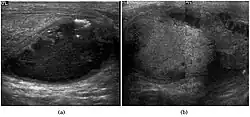

Fig. 7. Lymphoma. Lymphoma in a 61-year-old man. Longitudinal sonography shows an irregular hypoechoic lesion occupied nearly the whole testis.

Fig. 8. Primary Lymphoma. Longitudinal sonography of a 64-year-old man shows a lymphoma mimicking a germ cell tumor.

Clinically lymphoma can manifest in one of three ways: as the primary site of involvement, or as a secondary tumor such as the initial manifestation of clinically occult disease or recurrent disease. Although lymphomas constitute 5% of testicular tumors and are almost exclusively diffuse non-Hodgkin B-cell tumors, only less than 1% of non-Hodgkin lymphomas involve the testis.

Patients with testicular lymphoma are usually old aged around 60 years of age, present with painless testicular enlargement and less commonly with other systemic symptoms such as weight loss, anorexia, fever and weakness. Bilateral testicle involvements are common and occur in 8.5% to 18% of cases. At sonography, most lymphomas are homogeneous and diffusely replace the testis [Fig. 7]. However focal hypoechoic lesions can occur, hemorrhage and necrosis are rare. At times, the sonographic appearance of lymphoma is indistinguishable from that of the germ cell tumors [Fig. 8], then the patient's age at presentation, symptoms, and medical history, as well as multiplicity and bilaterality of the lesions, are all important factors in making the appropriate diagnosis.